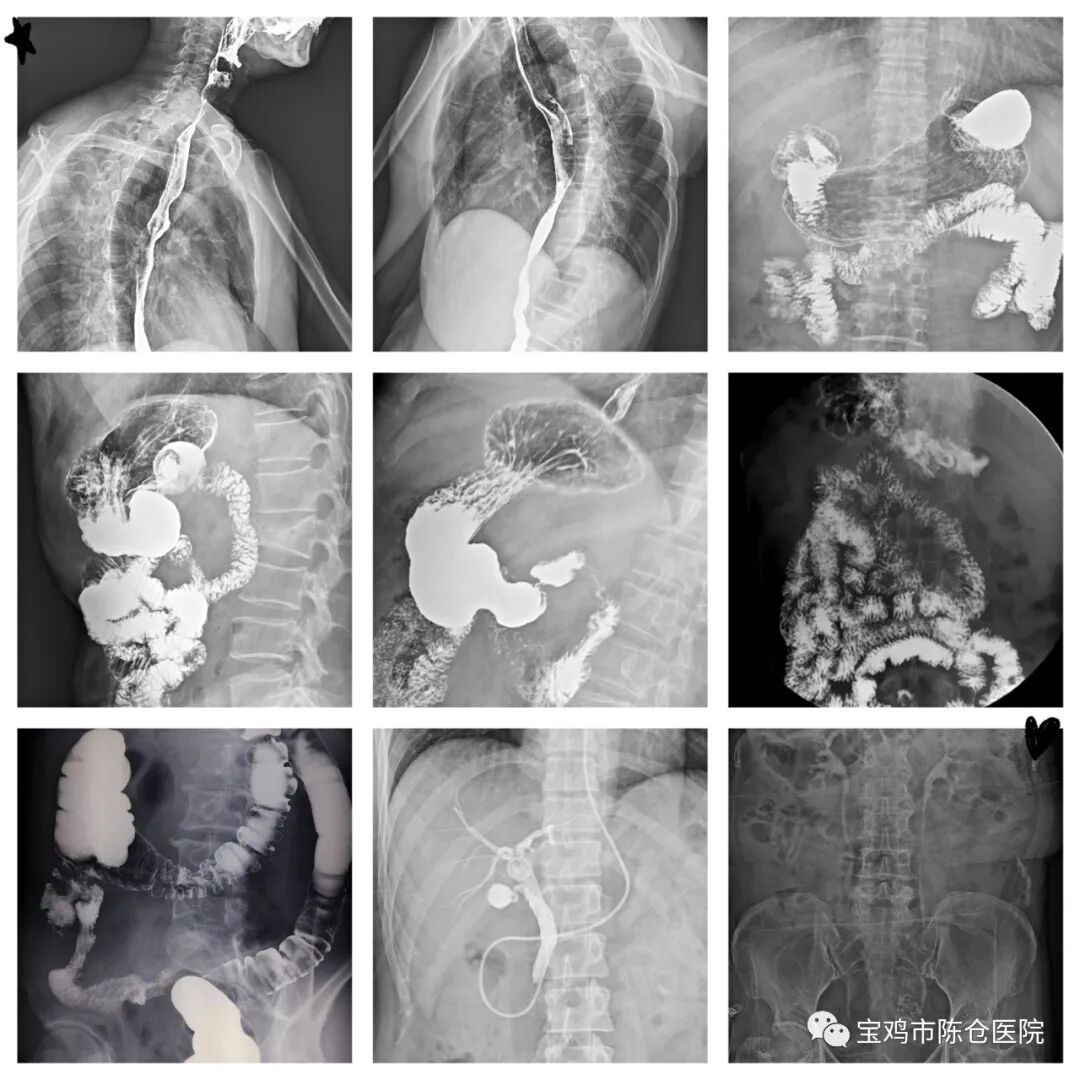

一直以来,胃肠道疾病的检查方法主要以X射线造影为主体,结合内镜及活检,近十余年来,随着CT、超声内镜、介入放射等新设备和新技术的应用,从不同侧面提供了很多诊断信息。但是胃肠疾病是复杂的,不同的症状有它特有的检查方式,数字胃肠机作为最常见的胃肠道疾病检查方法,有其临床的不可取代性。钡餐造影具有方便快捷、无创无痛的特点,而且检查费用也更易被接受。

造影检查可显示消化道病变的形态及功能改变,同时也可反应消化道某些病变范围及性质,常应用于诊断各种消化道疾病,如先天畸形、炎症、溃疡及肿瘤。很多胃肠道病变如胃下垂、胃扭转、胃底后倒(瀑布型胃)、胃粘膜脱垂、返流性食管炎、食管憩室、小肠憩室、贲门失弛缓症、十二指肠淤滞症等等,钡餐造影使病变显示更加直观清楚。